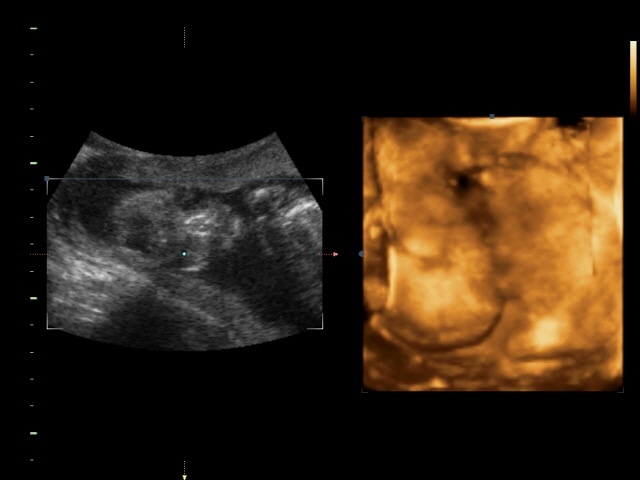

Пол малышаСходили мы на УЗИ вчера! Ходили с мамой и сыном, мужа в городе еще нет, но для него все записано на диск)) Итак, самое главное что все у нас хорошо, по мес 18 недель 4 дня(вчера ходили) по узи 19 недель 4 дня, перегнал почему то))) Малыш наш тихоня еще тот, я его почти не чувствую, спит постоянно, вот и на узи пришли, а он попой к нам повернулся, ручками закрылся, ножки поджал и все. Нииичего не увидишь(( я уже было расстроилась что всея, прийдется ждать следующего узи чтобы узнать пол, а ведь шла подготовленная, тортик поела сутра(начитавшись что сладкое приводиттак сказать малышей в движение))) но опытный врач все таки подлез к нашему малышу и.........барабанная дробь..................... МАЛЬЧИК!!! Мама попросила показать, тк по ее "правдивым и верным" подсчетам у меня должна была быть девочка( я ей поломала всю систему, тк до этого всем она считала и у всех сходилось, а у меня ни первый сын и второй-вместо девчонок)))-и тут на весь экран нам показали все наши достоинства, показали где и что расходится) а так как почти все узи мы смотрели в 4д сомнений у нас не было))) Весим мы 291гр, рост либо не написали либо я не нашла. Папа наш рад до безумия, как павлин распушил хвост и довольный))) Я тоже очень довольна, мне впринципе было все равно кто там живет, но как то больше хотелось сыну братика))) значит в третий раз пойдем за дочкой) даст Бог здоровье и благополучие и все будет хорошо!!!

Ну а вот собственно и сынок( младший))))